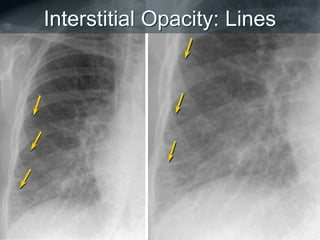

Opacidade Intersticial

 Doença localizada no interstício pulmonar, i.e.,

o septo alveolar e tecido conjuntivo que apoiam

os alvéolos

 Sinais cardinais:

• Linhas e/ou reticulação

• Pequenos nódulos bem definidos

 Padrão miliar

 DDX: Edema pulmonar, doenças pulmonares

intersticial (ex. fibrose pulmonar idiopática),

sarcoidose, infecção, tumor (linfangite

carcinomatosa), etc.

Interstitial Opacity: Lines

Interstitial Opacity: Lines & Reticulation